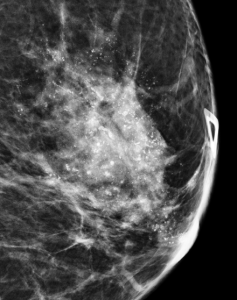

A spot magnification view in the ML projection is obtained:

How do you describe the distribution and morphology of the calcifications?

Explanation: These calcifications are in a segmental distribution, which is a roughly triangular shape which points towards the nipple. This pattern suggests that the calcifications are primarily located within the breast’s ductal system. The individual calcifications predominantly have discrete irregular shapes, are slightly coalescent, and are slightly larger than the fine pleomorphic type of calcification.